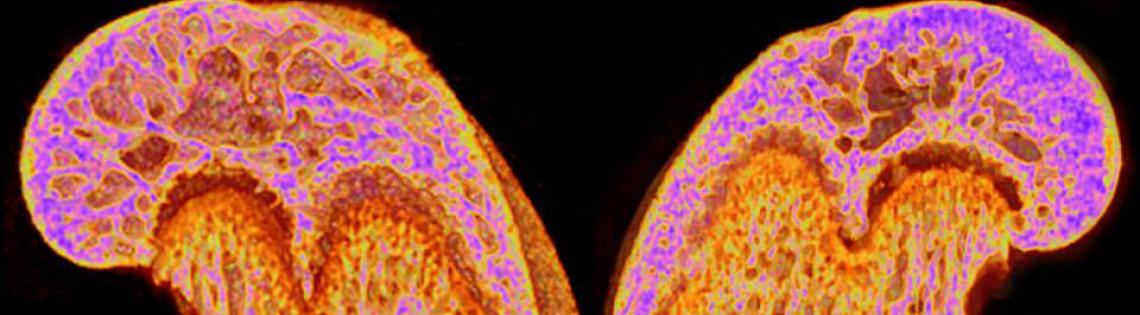

On the Cover

Micro-computed tomography (micro-CT) reconstructions of femurs of 9-week-old male mice. Images are mid-bone sagittal sections with gradient colors corresponding to bone mineral density.

Maria Morasso/NIAMS Laboratory of Skin Biology